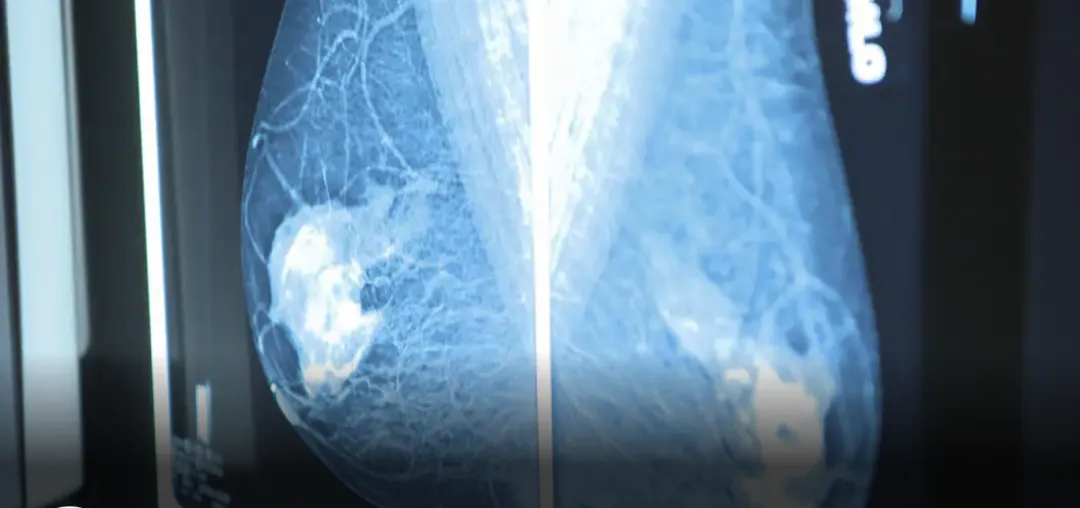

结直肠癌筛查通常涉及以下两种选择之一:家庭粪便免疫化学测试 (FIT) 是筛查工具之一,用于寻找粪便中的隐藏血液进行化验,通常在人们没有主要风险因素时提供。 当人们处于高风险或实际出现症状时,通常会提供肠镜检查。

安大略省结肠癌筛查计划的首席科学家 Jill Tinmouth 博士强调,目前还没有足够的证据表明对 50 岁以下人群进行筛查的好处会超过进行肠镜检查后的潜在危害。

这是一种侵入性测试,通常在患者处于麻醉状态时将一个灵活的内窥镜插入直肠。 虽然该测试通常是安全的,并且能够发现结肠内可能发生癌变的问题,但 Tinmouth 表示,当医生切除息肉时,它会带来轻微的风险——比如出血或刺穿结肠壁。